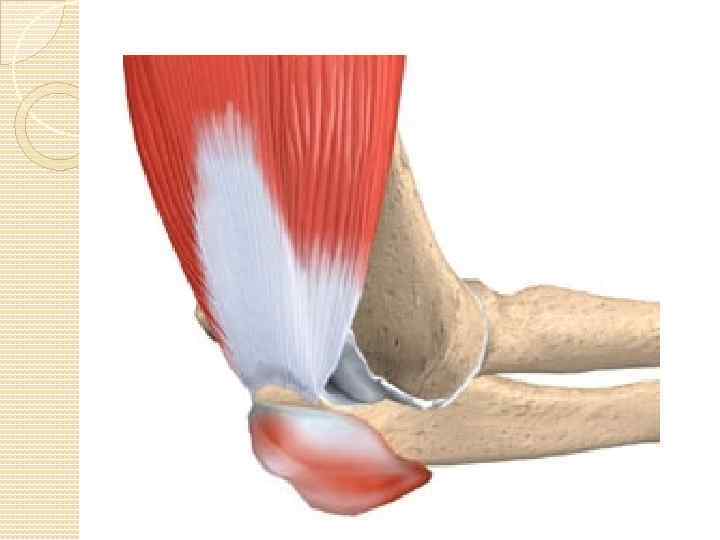

ЭПИКОНДИЛОЗ (АРТРОЗ ЛОКТЕВОГО СУСТАВА Эпикондилоз (артроз локтевого сустава) – нейродистрофические изменения в зоне надмыщелков плеча, где прикрепляются многие мышцы (длинные и короткий лучевой разгибатели кисти, локтевой разгибатель кисти, плечелучевая мышца и др. )